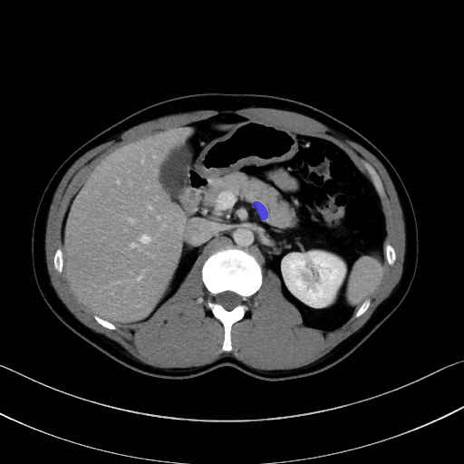

脾静脈の画像解剖

■起始:脾門で脾静脈枝が合流して本幹を形成。

■走行:膵体尾部の後面溝を右走し、膵頸部の後方で上腸間膜静脈(SMV)と合流して門脈を形成。

■主な流入枝:短胃静脈・左胃大網静脈・膵静脈、そして下腸間膜静脈(IMV)(変異あり)。